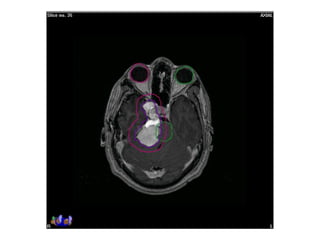

Response to treatment assessment

• ‘Lack of progression’ after conventional RT is considered response

• Increase in size as per RECIST criteria in considered progression

• High dose per fraction induce early regression in meningioma

• SRS (CyberKnife) induce early response with volume reduction

Pre-RT Post-RT: 6 mo

- No significant change in size of mass: stable disease

Response to treatmentassessment • ‘Lack of progression’ after conventional RT is considered response • Increase in size as per RECIST criteria in considered progression • High dose per fraction induce early regression in meningioma • SRS (CyberKnife) induce early response with volume reduction Pre-RT Post-RT: 6 mo - No significant change in size of mass: stable disease